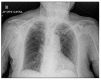

SARS-CoV-2 is the virus responsible for the COVID-19 pandemic, causing respiratory syndrome and other manifestations. The clinical consequences of the SARS-CoV-2 infection are highly heterogeneous, ranging from asymptomatic and mild to severe and fatal conditions, with the highest mortality rate reached among elderly people. Such heterogeneity appears strongly influenced by the host immune response, which in turn is profoundly affected by aging. In fact, the occurrence of a low-grade inflammation and a decline in specific immune defense is generally reported in older people. Although the low ability of B cells to provide primary and secondary specific responses with a consequent increase in susceptibility to and severity of virus infections is generally described in elderly people, we would like to present here the particular case of a 100-year-old woman, who recovered well from COVID-19 and developed a long-term memory against SARS-CoV-2. Following the infection, the patient's blood was tested with both a classical ELISA and a specific Cell-ELISA addressed to measure the anti-spike S1 specific IgG released in plasma or produced in vitro by memory B cells, respectively. While showing negative on classical serological testing, the patient's blood was positive in Cell-ELISA up to 1 year after the infection. Our observation highlights a potential mechanism of B cell-dependent, long-term protection in response to SARS-CoV-2 infection, suggesting that in a case of successful aging, the absence of specific antibodies in serum does not necessarily mean the absence of immune memory.